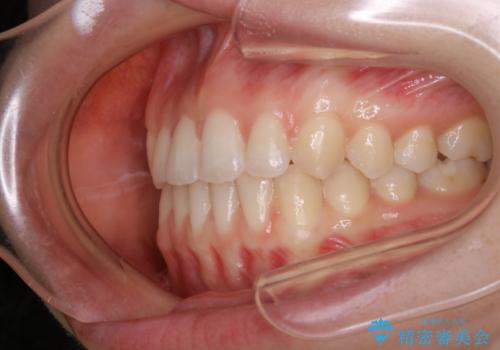

- 上下前歯のがたつきが気になるとご相談にいらした方です。

一見前歯のがたつきだけ改善させれば良い様に見えますが、このがたつきの原因は奥歯の嚙み合わせのズレからくるものであったため、インビザラインFULLで噛み合わせの改善から行っていきました。前歯の角度も改善されたために頑張って唇を閉じる必要がなくなり、横顔のシルエットも綺麗になりました。

前歯のがたつきだけを治そうとした場合、噛み合わせは二の次なってしまう事が多く、せっかく綺麗になった歯並びも後戻りしやすくなります。奥歯の噛み合わせからしっかり機能させることで、長期間にわたって綺麗な歯並びを保ちやすくなります。

インビザライン20時間以上正しく装着していただいたおかげもあり、短期間で治療することが出来ました。